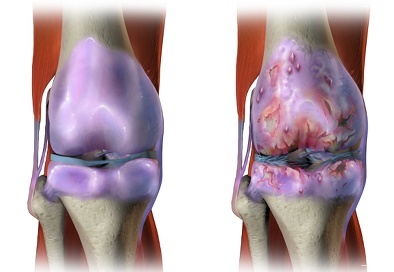

무릎 퇴행성관절염은 무릎의 연골(물렁뼈)이 닳아 없어지며 염증이 발생하는 질환입니다. 무릎을 오랫동안 사용해 온 노년층에서 많이 발병합니다. 하지만 요즘은 젊은 층에서도 퇴행성관절염으로 고생하고 있는 사람들이 많습니다. 방치하면 퇴행성관절염의 증상과 치료방법에 대해 확인하시기 미리 예방하시기 바랍니다.

퇴행성관절염은 시간이 흐를수록 연골 손상 범위가 넓어집니다. 퇴행성관절염을 방치해 무릎 위아래 뼈가 맞닿을 정도로 연골이 손상되면 관절 전체를 인공관절로 대체해야 합니다. 퇴행성관절염은 서서히 진행되는 탓에 병을 인지하지 못해 방치하기 쉬운데 초기에 발견해 치료하면 진행 속도를 늦출 수 있습니다.